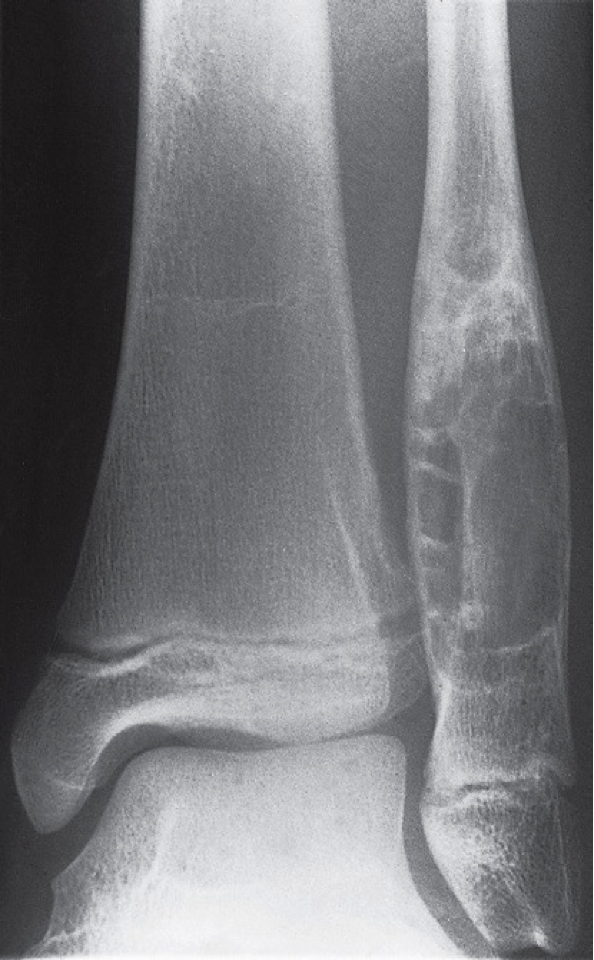

Expansion of the cortex due to fibrous dysplasia.